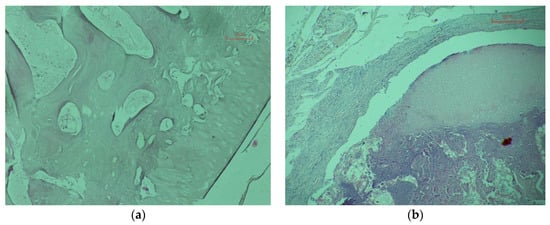

On the 110th day after transplantation in animals of the control and experimental groups above and to the left is the connective tissue surrounding the graft. The transplanted bone is represented by a site of hyaline cartilage (above) to which from the inside a portion of the resorbable bone matrix is adjacent. A similar picture is observed both in the control and in the experimental group (see Figure 7b).

The results of a morphological study indicate the maintenance of the diffusion of substances and the migration of cells through a worked-out construct.

Figure 7. Micrograph of bone X400: The 110 days after transplantation, control animal (a); 110 days after transplantation, experienced animal (b).